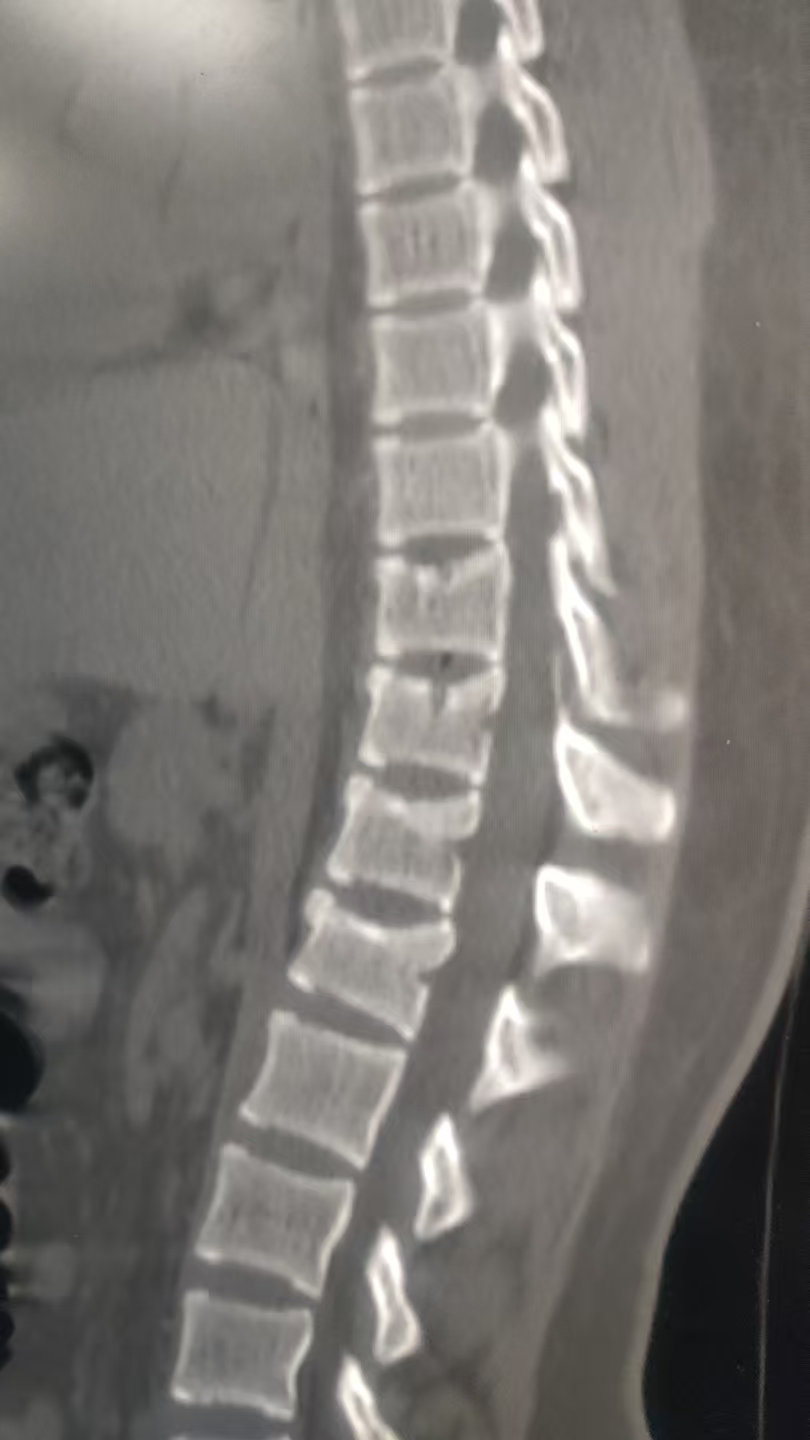

我妈是环卫工,去年七月份,,去上班开着环卫电三轮路上与一个骑电动自行车女学生相撞,我妈在机动车道正常行驶,在自行车道行驶的女学生看到前面有施工围挡,就从小路口拐到机动车道,这时与我妈的电三轮相撞,我妈说女学生骑的比较快,她的电动车从侧后面撞击了我妈的三轮车,女学生倒地受伤。一个星期后,到交警队定则,看了录像,是学生直接撞击的我妈三轮侧面。定的我妈次要责任,女孩主要责任,理由是我妈的电动三轮未在非机动车道行驶,就算是机动车,也没有驾照。 交警定的合理吗? 现在女孩定了居然定了伤残九级,起诉了我妈。 交警这责任划分 还能翻案吗? 另外请有经验的老师 看看,女孩的医生诊断是腰椎1压缩性骨折 胸椎10~12轻度压缩性骨折,应该都没到1/3。能评到十级伤残吗?

• 根据《人体损伤致残程度分级》标准:十级伤残:一椎体压缩性骨折(压缩程度达1/3),或一椎体粉碎性骨折。 ​九级伤残:二椎体压缩性骨折,或一椎体粉碎性骨折伴椎管内骨性占位等。 你描述的伤情是“腰椎1压缩性骨折、胸椎10~12轻度压缩性骨折,压缩都不到1/3”: 如果每一节椎体压缩均未达到1/3,且无粉碎性骨折或手术治疗,通常不构成九级伤残,甚至可能不构成十级伤残。 ​如果存在手术治疗、粉碎性骨折或其他并发症,则可能影响最终评定。 建议你方在诉讼中申请重新鉴定,由法院委托有资质的机构重新评估伤残等级。

• 1. 责任划分合理性: 交警定责合理——电三轮属非机动车,应走非机动车道;无驾照也属违规,所以你妈负次要责任。若不服,需在收到责任认定书3日内申请复核,但翻案概率低(有录像证明学生撞击,但你妈有车道/驾照违规)。 2. 伤残等级问题: 骨折压缩未到1/3,通常评不上九级,大概率也达不到十级(十级一般要求压缩≥1/3)。可向法院申请重新鉴定,以新结果为准。 核心:责任划分难推翻,伤残等级可申请重新鉴定,未达1/3难评上伤残。

女孩有腰椎1 和 胸椎至少3个节段的压缩性骨折。根据标准,二椎体压缩性骨折即可构成九级伤残。女孩的骨折数量远超这个标准,因此被评定为九级伤残是有依据的,甚至可能构成更高等级(如八级),具体要看压缩程度和功能受限情况。

• 一、关于交警定责是否合理 1. 定责依据: - 对方(女学生):违反《道路交通安全法》(未确保安全通行),且从非机动车道突然拐入机动车道,是事故主要诱因。 - 你母亲:电动三轮车未在非机动车道行驶,且无相应驾驶证,存在过错。 - 交警据此认定女学生主要责任、你母亲次要责任,在法律上具有合理性。 2. 复核空间: - 若对责任认定有异议,可在收到认定书之日起3日内向上一级交管部门申请复核。 - 复核重点可放在:电动三轮车的属性认定、你母亲作为环卫工在作业时的通行特殊性、对方突然变道的危险性等。 二、关于伤残等级是否过高 1. 鉴定依据: - 鉴定机构依据《人体损伤致残程度分级》5.9.6.2条“二椎体压缩性骨折”,结合女孩腰1、胸10-12椎体压缩性骨折的伤情,评定为九级伤残,符合标准。 - 即使单椎体压缩未达1/3,多椎体同时骨折的伤情已满足九级伤残的评定条件。 2. 重新鉴定建议: - 若对鉴定结论有异议,可在诉讼中向法院申请重新鉴定。 - 需提供充分证据,证明鉴定机构在伤情认定或适用标准上存在错误。 三、诉讼应对策略 1. 追加被告: - 你母亲是在执行工作任务时发生事故,可申请追加其用人单位(环卫公司)为共同被告,由公司在交强险外按责任比例承担赔偿责任。 2. 保险理赔: - 若电动三轮车投保了保险,应及时通知保险公司,由其在保险限额内承担赔偿责任。 3. 证据准备: - 收集事故现场照片、视频、证人证言,证明对方突然变道的事实。 - 准备你母亲的工作证明、工资流水,用于证明其行为属于职务行为。

• 虽然不能复核,但在法院审理时,您可以向法官提出对责任划分的异议,并提交证据(如现场录像)。法官会审查认定书作为证据的效力,如果确有错误,法院可以不采信该认定书,重新划分赔偿比例。从您描述的“压缩不到1/3”来看,评九级确实偏高了,评十级的可能性更大。